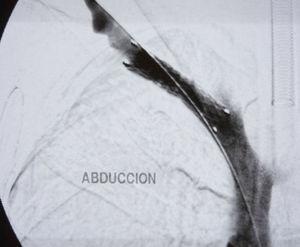

With the diagnosis of deep vein thrombosis of the upper right limb, we decided to carry out phlebography with a hollow fibrinolysis guide (0.035mm) and at the same time intra-thrombus fibrinolysis was initiated with urokinase at an initial dose of 250 000U and later 60 000U/h. We ordered a series of radiological controls to follow the evolution and to be able to reposition the catheter. Forty-eight hours afterwards, and after having confirmed the lysis of the thrombus, it was decided to suspend fibrinolysis, perform angioplasty with an 8mm×40mm balloon, and initiate anticoagulation until surgery (Fig. 1). Four weeks afterwards, decompression surgery was performed with transaxillary resection of the first rib. On the routine post-operative phlebography examination, significant residual stenosis and the presence of abundant collateral circulation were observed, and an 8mm×40mm stent was implanted to correct the stenosis (Fig. 2). Currently, one year after surgery, the patient remains asymptomatic.

Doppler ultrasound5 is the first diagnostic technique required. In expert hands, it is very sensitive (78%–100%) and specific (82%–100%).6 The following step is phlebography, with which thrombosis of the subclavian-axillary vein in the costoclavicular union and presence of abundant collateral circulation can be observed.1 If an obstruction is not observed, the presence of collateral circulation always indicates a certain degree of stenosis. Provocation maneuvers, such as the separation of the extremity, may help in the diagnosis.1